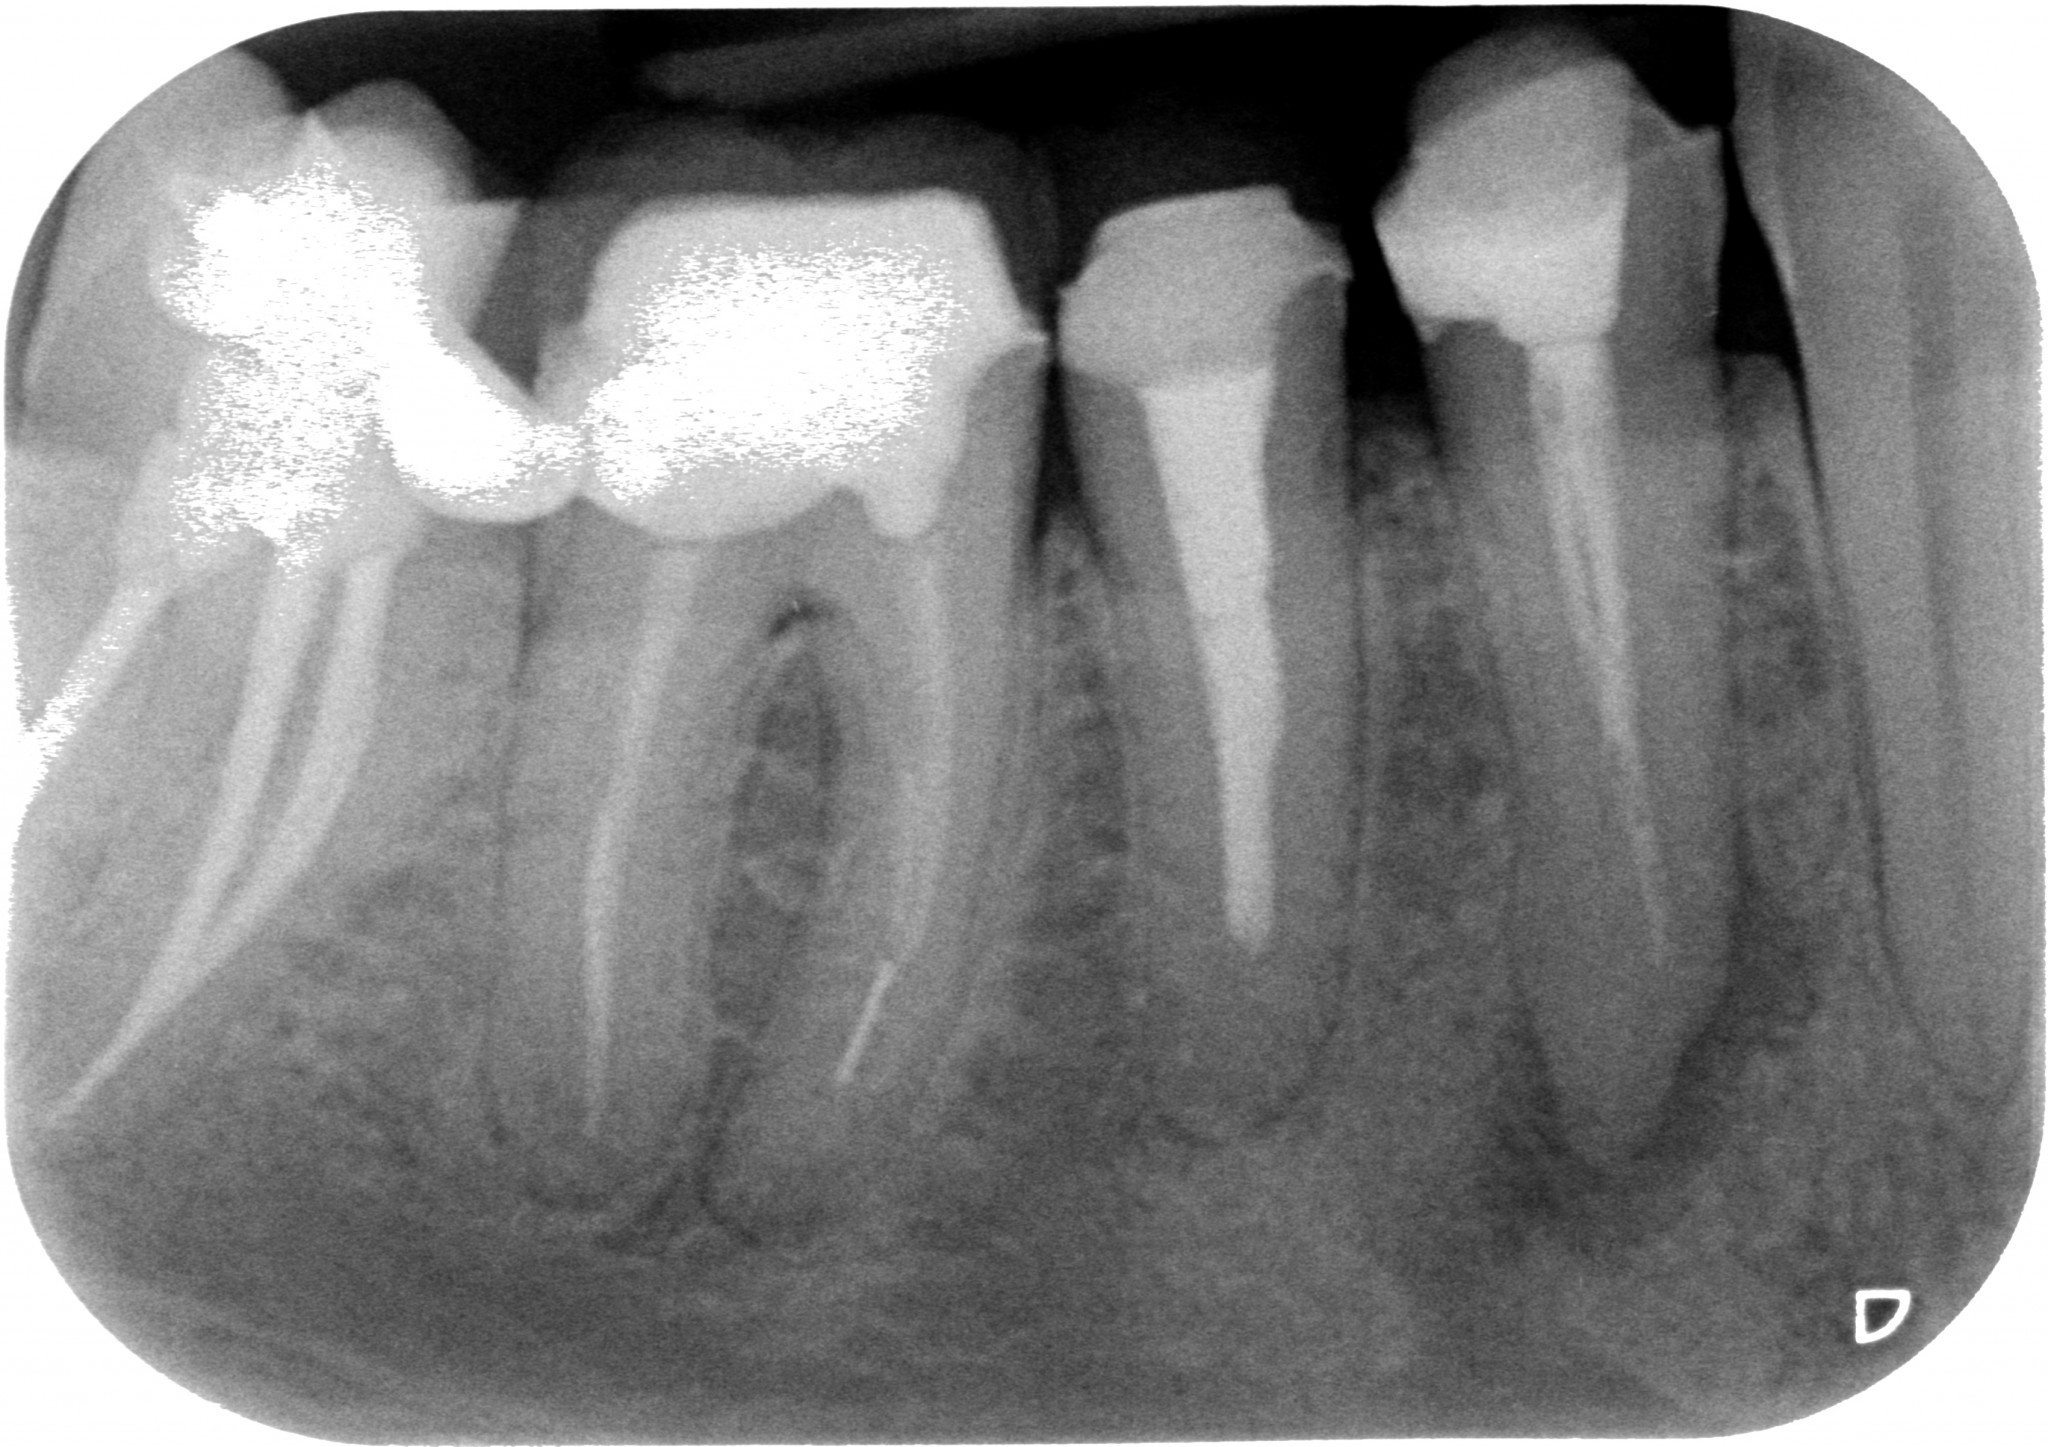

E arrivandomi il microscopio ho cominciato a trovare anatomie assurde a josa…E le riuscivo a chiudere solo coi thermafil…anche se in realtà evidentemente credevo solo di farlo, perché era impossibile. Guarda questo primo premolare inferiore che ho ritrattato un mesetto fa…forcazione a 5 mm dal fondo del dente…in pratica una IV classe di Weine…Secondo te con cosa l’ho chiuso? ?

Thermafil - Anatomia difficile iniziale Thermafil - Anatomia difficile lunghezze Thermafil - Anatomia difficile finale